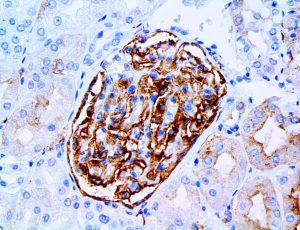

This activation induces inflammatory monocytes to highly express IL-6, starting a localized and then systemic cascade effect that results in hyperproduction of IL-6, which accelerates the inflammatory process. Because IL-6 also increases vascular permeability, excessive levels cause blood vessels to become very leaky. This, along with clotting factors released from vascular endothelial cells, stimulates the coagulation cascade, resulting in microthrombosis (tiny clots), which leads to ischemia and tissue death of the kidney, intestines, heart, liver, brain and extremities.